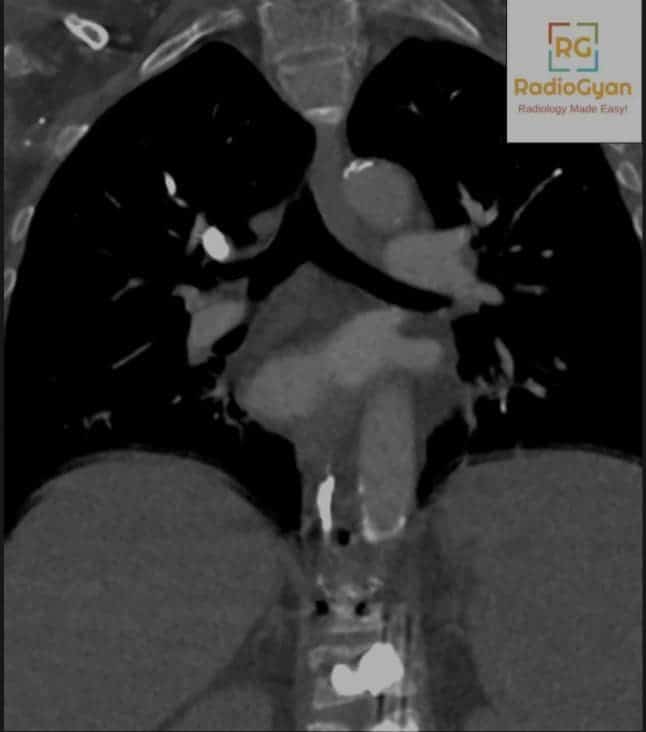

In our recent article: Pulmonary embolism diagnosis: What else the radiologist MUST report! We had posted the above image. This patient presented with breathlessness after vertebroplasty. Here are more images:

To confirm that these are pulmonary cement embolism and not dense contrast I have shown the same images with HU values. HU values of the thrombus correspond to that of the vertebroplasty cement.

Final diagnosis: Pulmonary cement embolism after vertebroplasty

- Seen as dense filling defects along the distribution of pulmonary arteries.

- Branching high-attenuation area of more than 500 HU (as shown in the figure above) along the expected course of the pulmonary artery.